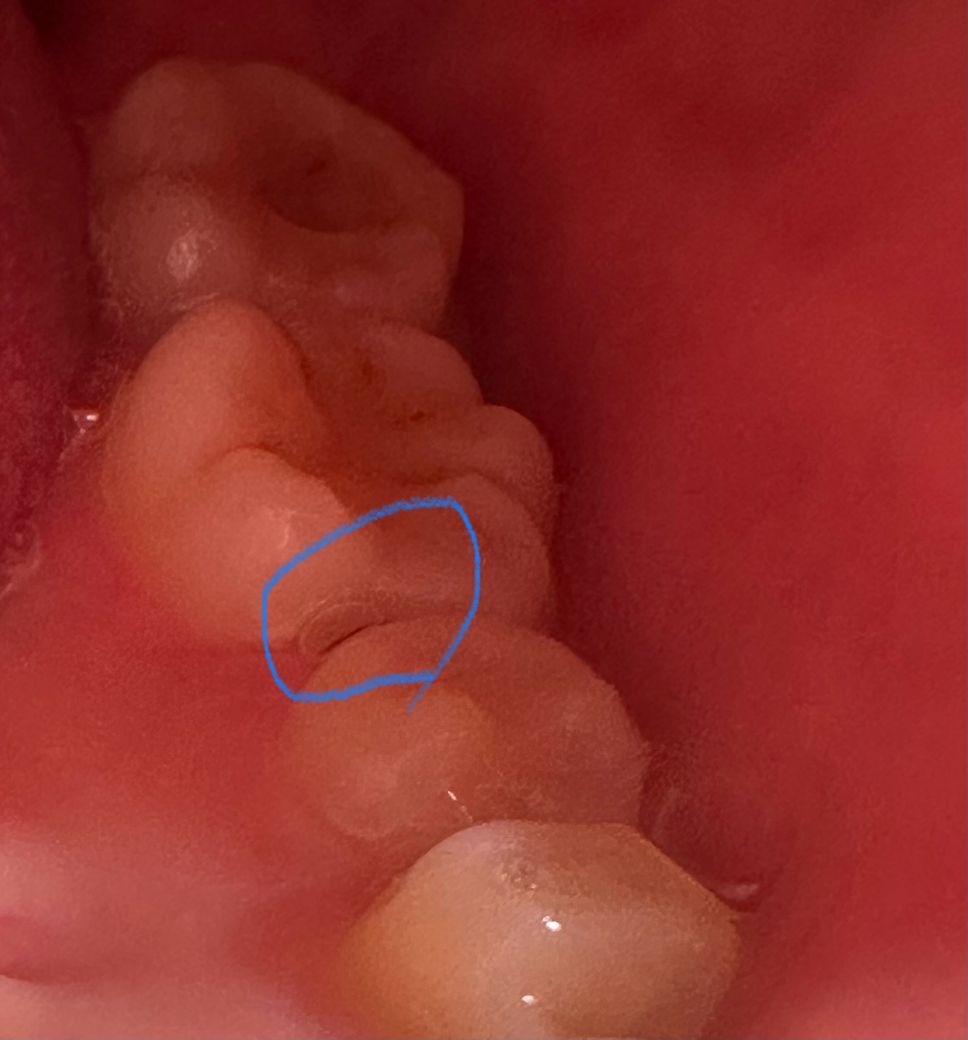

충치인가요? 잇몸선라인? 치아? 검은색이 보입니다

이거 충치일까요? ㅠㅠ 스케일링은 두 달전에 받았고 매일 치실 양치를 열심히 하는데 어느순간 검은선? 같이 보입니다.. 치과가기가 너무 무서워요 충치일까봐

이전에 충전한 재료 주변의로 착색이 생긴것일수 있습니다.

충치가 아닐 가능성이 높아보이지만 사진만으로는 명확히 알 수 없어 치과 검사 받아보시는 게 좋겠습니다.

치아 사이에 착색이 됫을 가능성이 잇어 보이니 일단은 양치나 치실로 관리를 해보시는게 좋을것같습니다.